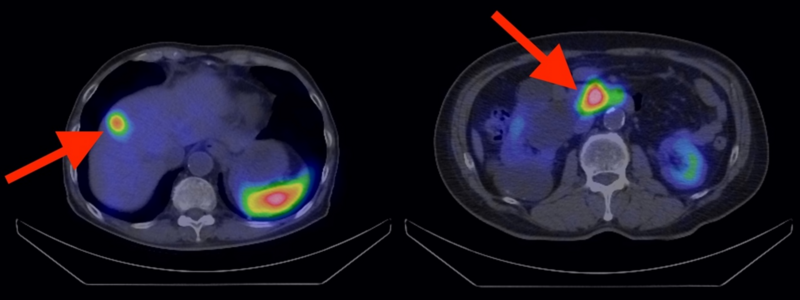

CT検査やMRI検査では見つけにくい小さな病変や、転移の有無を確認する際に、ソマトスタチン受容体シンチグラフィ(Somatostatin Receptor Scintigraphy:SRS)という検査を行うこともあります。この検査は、神経内分泌腫瘍の多くが持つ、ソマトスタチン受容体という特定のタンパク質を利用した画像検査です。

ソマトスタチン受容体と結合する薬を注射し、専用のカメラで撮影すると、腫瘍のある場所が映し出されるため、病変の位置を特定することが可能になります。

なお、詳しくは後述しますが、放射線治療の適応を判定する目的でも用いられます。